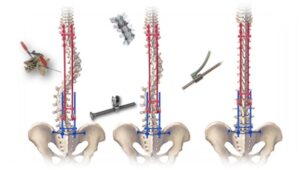

Conheça um pouco mais do blog informativo do neurocirurgião Dr. Diego Ramos. Tópicos sobre escoliose, neucirurgia adulta e pediátrica são abordados para trazer um pouco de conhecimento para pacientes ao redor do mundo.